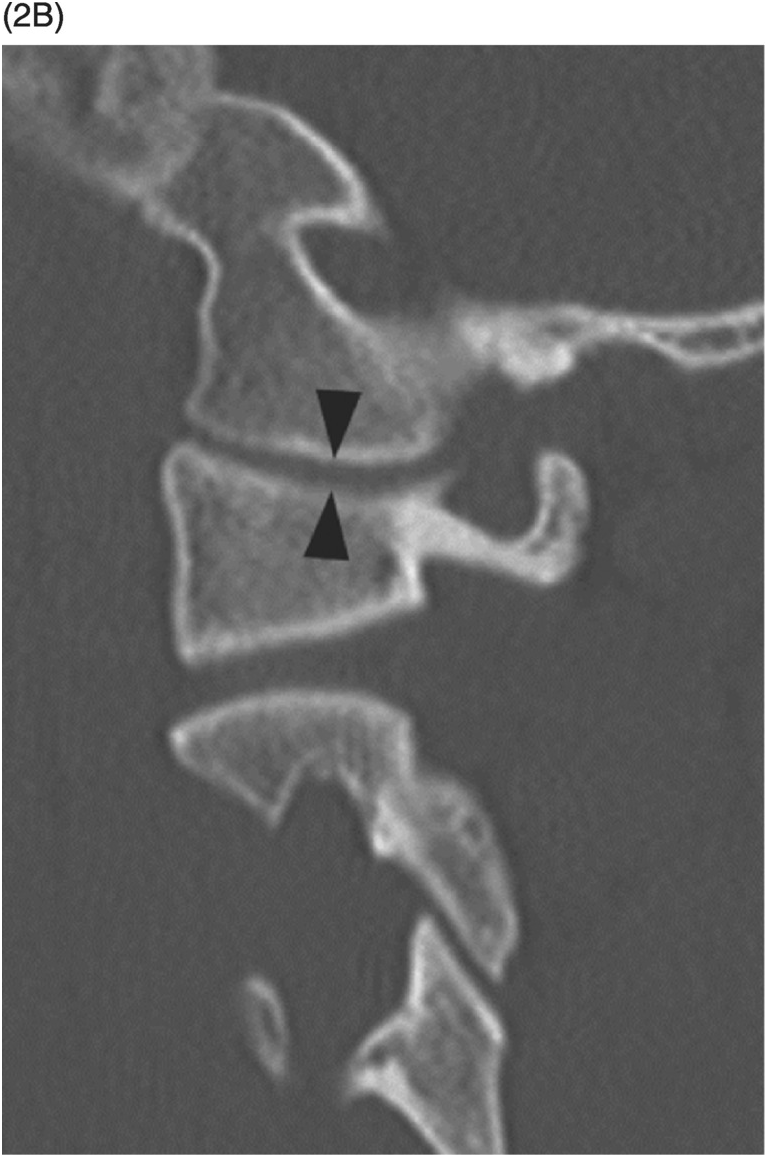

MRI and CT Atlas of Correlative Imaging in Otolaryngology

MRI and CT Atlas of Correlative Imaging in Otolaryngology

Axial non-contrast (A) and contrast (B) CT brain at, Traumatic injury to the unfused anterior arch of C1 in the,